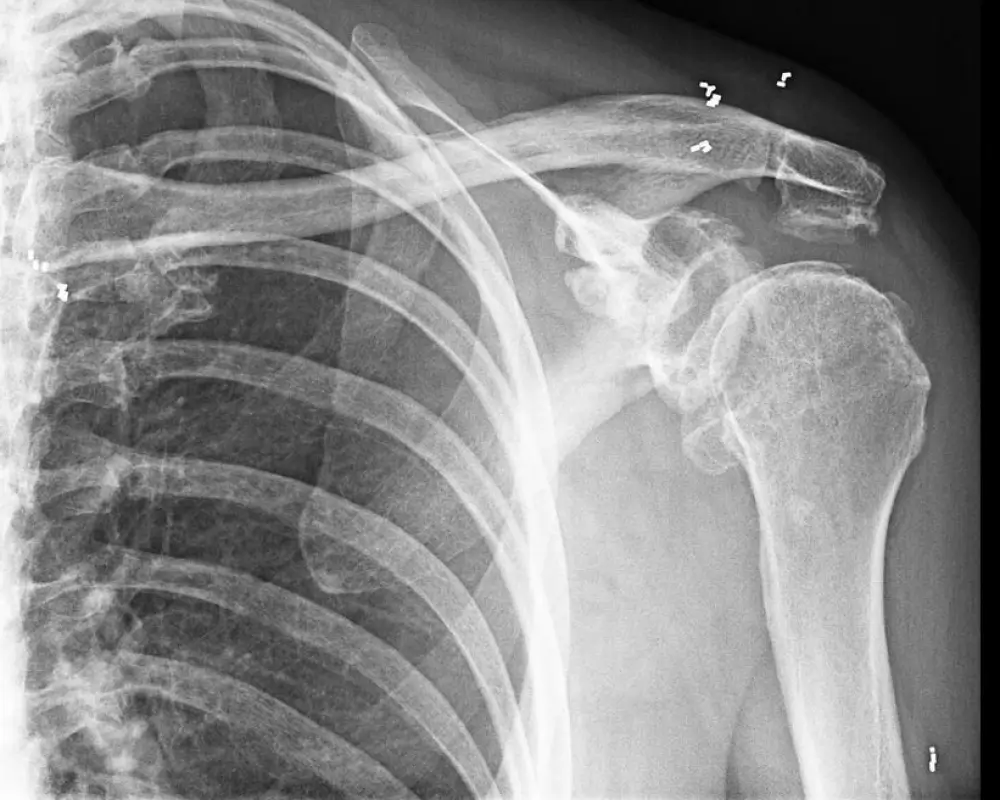

Schultergelenke

Verbessert Gelenkfunktion und mindert chronische Entzündungen.

Nach ausführlicher Diagnostik und Beratung werden unter lokaler Betäubung winzige 1–2 mm lange Segmente aus 24-karätigem Golddraht mit einer Hohlnadel rund um das betroffene Gelenk implantiert. Die Goldstücke verbleiben dauerhaft außen an der Gelenkkapsel, wandern nicht und entfalten dort ihre entzündungshemmende Wirkung – ganz ohne Gelenkoperation, Nachoperationen oder Antibiotika­therapie.